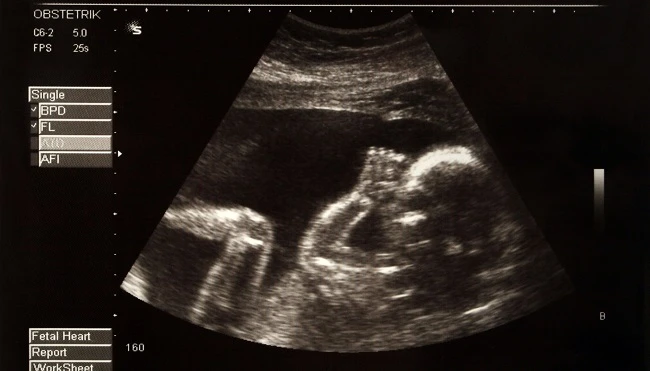

Τι μπορούν να κάνουν τα μωρά ενώ βρίσκονται ακόμη στην μήτρα;

Η ζωή των μωρών ξεκινά πολύ πριν καν κάνουν το ντεπούτο τους στον κόσμο. Μάλιστα, οι επιστήμονες έχουν ανακαλύψει πως τα έμβρυα μέσα στην μήτρα είναι ικανά για πολλά θαυμαστά πράγματα. Εσείς γνωρίζατε τα παρακάτω;

Χαμογελούν!

Ναι, είναι αλήθεια! Οι 4D υπέρηχοι αποκάλυψαν πως τα μωρά μπορούν και χαμογελούν μέσα στην μήτρα από την 26η εβδομάδα. Πόσο χαριτωμένο;!

Κλαίνε!

Είναι λίγο αποκαρδιωτικό, αλλά όπως και να το κάνουμε πρέπει με κάποιον τρόπο να «προπονηθούν» και σε αυτό, μιας και το κλάμα είναι σημαντικό εργαλείο επικοινωνίας για τα νεογέννητα.

Έχουν λόξυγκα!

Αυτό είναι πραγματικά αστείο! Τα μωρά μπορεί να έχουν λόξυγκα ήδη από το πρώτο τρίμηνο της εγκυμοσύνης. Οι μητέρες συνήθως δεν το καταλαβαίνουν!

Αντιδρούν στο φως!

Τα μάτια των μωρών παραμένουν ερμητικά κλειστά μέχρι και τον 7ο μήνα, απόλυτα λογικό εάν σκεφτεί κανείς πως η όραση είναι η τελευταία αίσθηση που αναπτύσσουν. Από τον 7ο μήνα, όμως, και μετά τα μωρά, ως δεινοί κολυμβητές, ανοίγουν τα ματάκια τους και, αφού δεν έχουν και πολλά να δουν, αντιδρούν στο φως που φιλτράρεται από την κοιλιά σας προσπαθώντας να απομακρυνθούν από αυτό.

Έχουν γευστικές προτιμήσεις!

Ό,τι τρώτε μεταφέρεται στο μωρό σας και έτσι τα έμβρυα παίρνουν μια γεύση του κόσμου πολύ πριν δοκιμάσουν την πρώτη τους τροφή. Μάλιστα, οι έρευνες δείχνουν πως το μωρό μπορεί να παρουσιάσει συγκεκριμένες γευστικές προτιμήσεις ήδη από την 15η εβδομάδα, αφού τείνουν να καταπίνουν περισσότερο αμνιακό υγρό όταν αυτό είναι γλυκό!

Κάνουν αναπνευστικές κινήσεις!

Τα έμβρυα λαμβάνουν το απαιτούμενο οξυγόνο από τον ομφάλιο λώρο, ενώ παίρνουν την πρώτη τους ανάσα με το που βγουν στον έξω κόσμο. Ωστόσο, οι επιστήμονες έχουν βρει πως τα μωρά κάνουν αναπνευστικές κινήσεις ήδη από την μήτρα.

Ουρούν!

Επειδή το έμβρυο καταπίνει και χωνεύει αμνιακό υγρό, είναι απολύτως φυσικό να απελευθερώνει ούρα μέσα στην μήτρα. Πριν βιαστείτε να πείτε «αηδία», σκεφτείτε πως είναι πεντακάθαρα και πως σύντομα θα έχετε μαζί τους μια πολύ πολύ στενή σχέση!

Πιπιλούν το δάχτυλό τους!

Έχει παρατηρηθεί πως πολλά μωρά από τον 6ο μήνα πιπιλούν το δάχτυλό τους και, μάλιστα, δείχνουν προτίμηση στο αντίχειρα του δεξιού τους χεριού.

Βλέπουν όνειρα... μάλλον!

Οι υπέρηχοι έχουν δώσει στοιχεία στους ερευνητές που υποδεικνύουν πως τα έμβρυα όταν κοιμούνται κινούν γρήγορα τα μάτια τους (ύπνος REM-από το αγγλικό Rapid Eye Movement), κάτι που πιθανώς υποδηλώνει πως βλέπουν όνειρα. Ωστόσο, κάτι τέτοιο δεν είναι σίγουρο, αφού ο εγκέφαλος των εμβρύων δεν είναι –ακόμη τουλάχιστον-δυνατόν να παρακολουθηθεί.